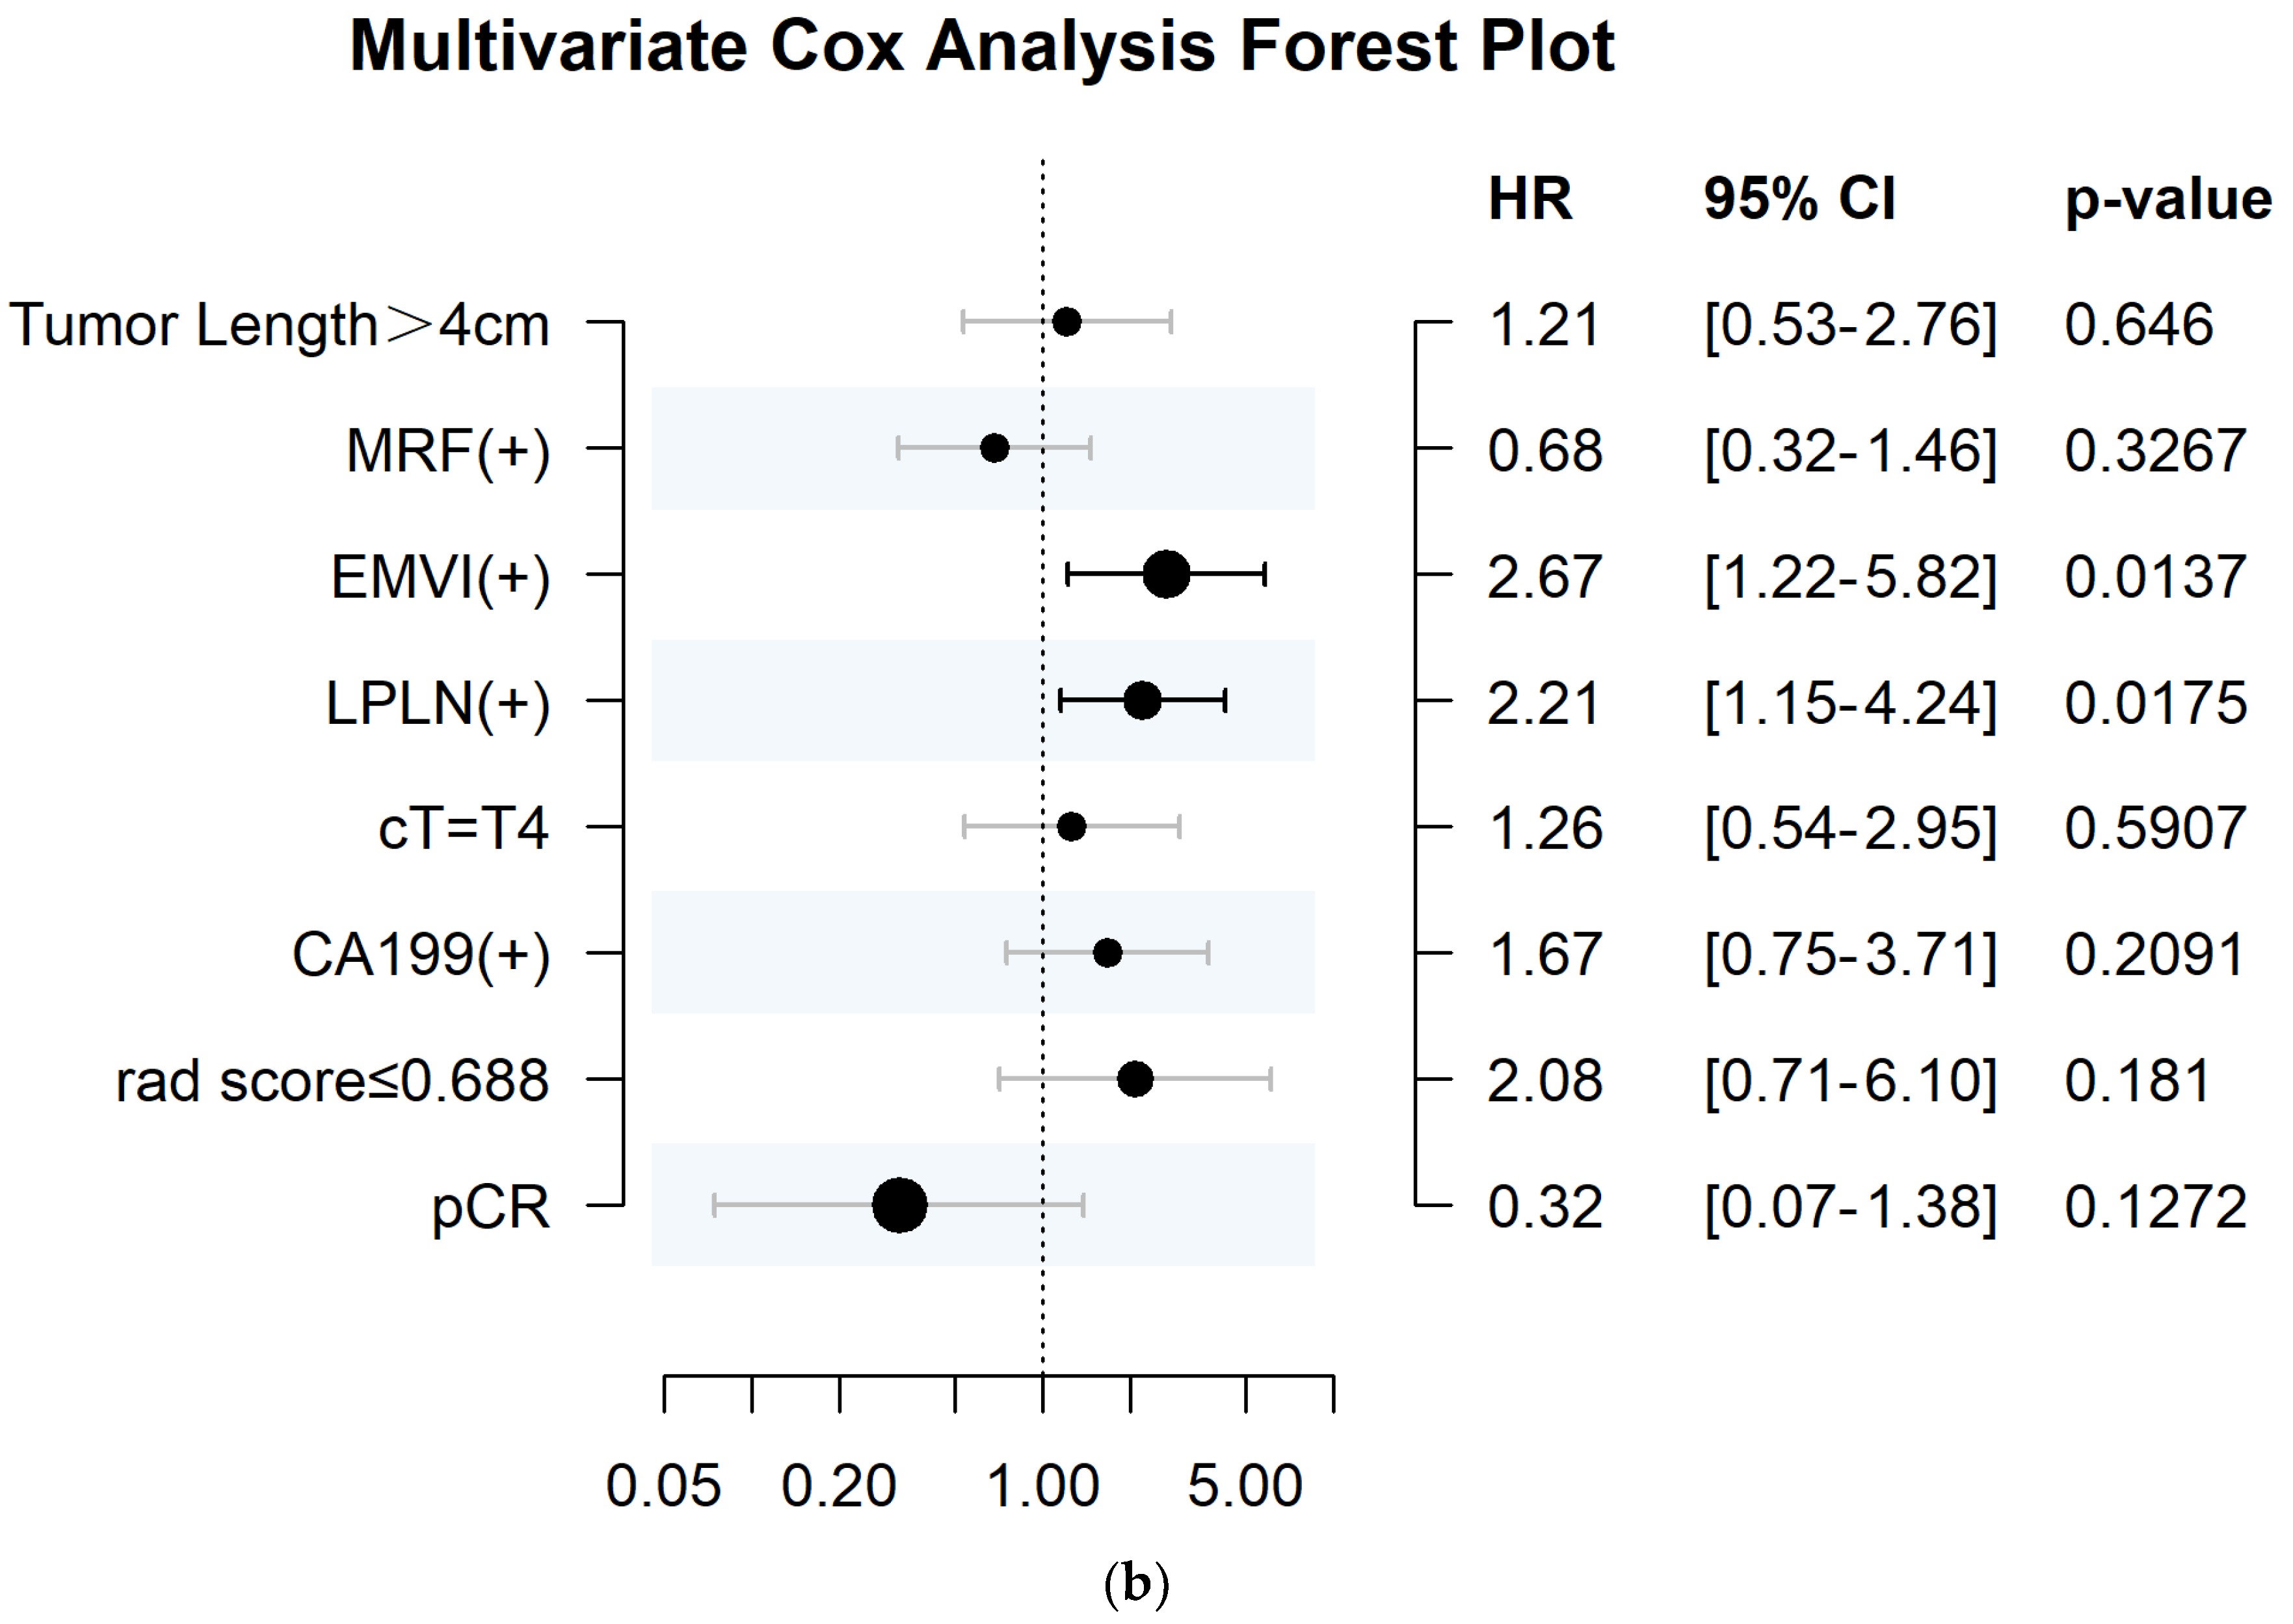

3.5. The Association between Radscore and Disease–Free Survival

| Factor | Number (n) | Univariate Cox Analysis | Multivariate Cox Analysis | |||

|---|---|---|---|---|---|---|

| HR (95%CI) | p | C–Index | HR (95%CI) | p | ||

| Tumor length | 0.016 | 0.585 | 0.53 | |||

| ≤4 cm | 86 | 1 | ||||

| >4 cm | 123 | 2.328 (1.144–4.736) | 1.304 (0.57–2.985) | |||

| MRF | 0.018 | 0.591 | 0.356 | |||

| Negative | 137 | 1 | ||||

| Positive | 72 | 2.05 (1.119–3.755) | 0.704 (0.335–1.482) | |||

| EMVI | <0.001 | 0.678 | 0.009 | |||

| Negative | 120 | 1 | ||||

| Positive | 89 | 4.102 (2.098–8.018) | 2.799 (1.292–6.062) | |||

| LPLN | <0.001 | 0.636 | 0.015 | |||

| Negative | 151 | 1 | ||||

| Positive | 58 | 3.42 (1.863–6.281) | 2.251 (1.17–4.332) | |||

| cT | 0.036 | 0.555 | 0.654 | |||

| T3 | 186 | 1 | ||||

| T4 | 23 | 2.245 (1.036–4.862) | 1.211 (0.524–2.801) | |||

| CA19–9 | 0.014 | 0.234 | ||||

| Negative | 185 | 1 | ||||

| Positive | 24 | 2.461 (1.177–5.146) | 1.629 (0.73–3.638) | |||

| radscore | 0.034 | 0.576 | 0.78 | |||

| ≥0.688 | 52 | 1 | ||||

| <0.688 | 157 | 2.303 (1.065–4.977) | 1.126 (0.489–2.595) | |||

| pCR | 0.007 | 0.59 | 0.103 | |||

| No | 165 | 1 | ||||

| Yes | 44 | 0.176 (0.043–0.728) | 0.294 (0.068–1.279) | |||